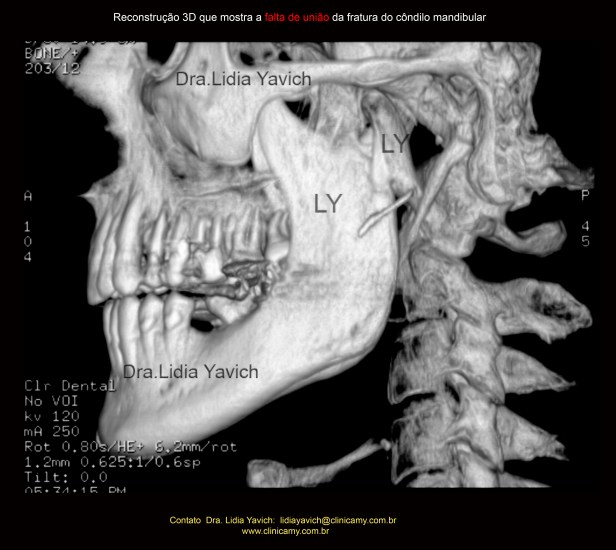

Foi solicitada uma TC (tomografia computadorizada) para obter um diagnóstico mais preciso.

TC: cortes sagitais confirmando a falta de união total da fratura do côndilo mandibular, quatro meses após a cirurgia.

TC: cortes frontais confirmando a falta de união total da fratura do côndilo mandibular, quatro meses após a cirurgia.

Reconstrução em 3D mostrando a falta de união total da fratura do côndilo mandibular, quatro meses após a cirurgia.

Outra reconstrução em 3D mostrando a falta de união total da fratura do côndilo mandibular, quatro meses após a cirurgia.

Reconstrução em 3D mostrando a falta de união do côndilo mandibular esquerdo após quatro meses da cirurgia e a posterior união do côndilo mandibular após o tratamento neurofisiológico.